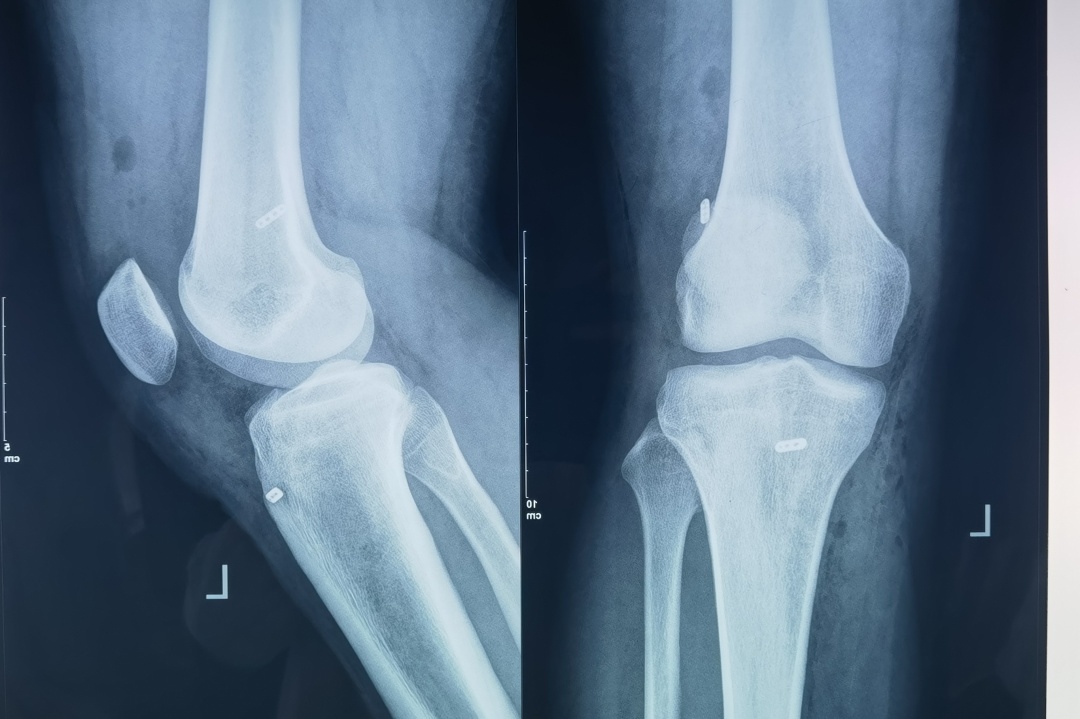

患者为男性,17岁,上体育课时不慎摔倒,疼痛难忍,诊断为:左膝关节前交叉韧带撕裂,左膝关节内侧副韧带损伤、内侧半月板撕裂等。

术前

“膝关节前交叉韧带损伤是常见的运动损伤,会严重影响患者的下肢功能,导致活动受限、关节不稳。我院目前可以开展膝关节镜下前交叉韧带损伤全内重建技术,该手术方式较传统手术方式有更多的优势:钻取骨道更短,保留更多的骨质,只需切取一条自身肌腱,创伤更小,移植物的双皮质坚强固定,更有利于患者术后早期康复。”榆林市星元医院关节外科王彦东主任医师介绍。

为进一步开展治疗,帮助患者康复,星元关节外科医护团队进行了充分的病例讨论,制定了详实的治疗方案和周密的手术方案。在取得患者及家属同意,关节外科刘增亮主任、王彦东主任医师、白马恒副主任医师成功为患者实施了“前交叉韧带损伤关节镜下全内重建术”,术后患者恢复良好。

术后